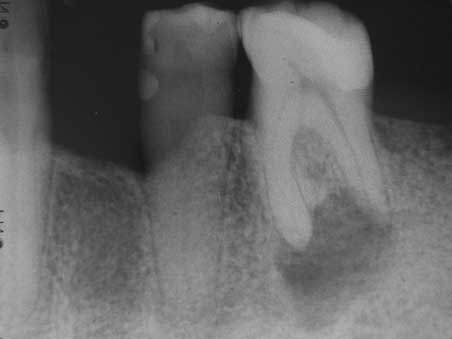

Apikale Aufhellung 001 Bild 1

Veröffentlicht 10. Februar 2009 am 452 × 339 in Apikale Aufhellung (1)